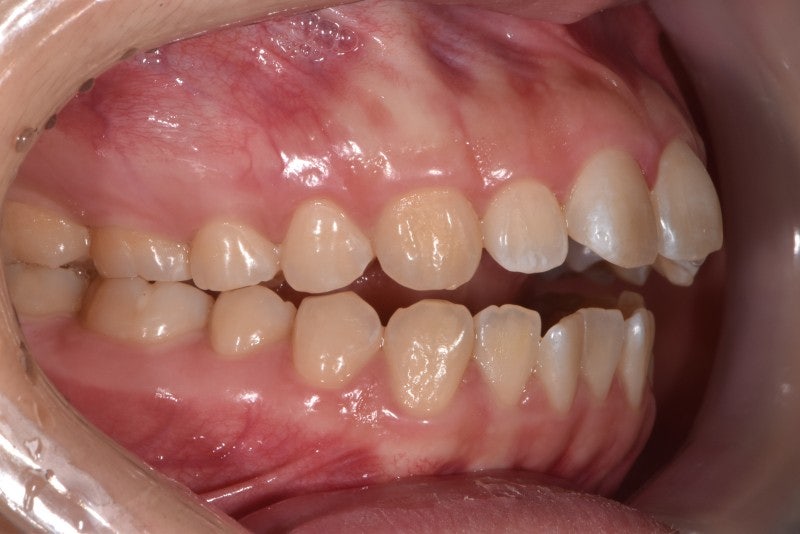

-비수술적 안면비대칭교정 사례-사례1(일측성 비대칭 상악연전)